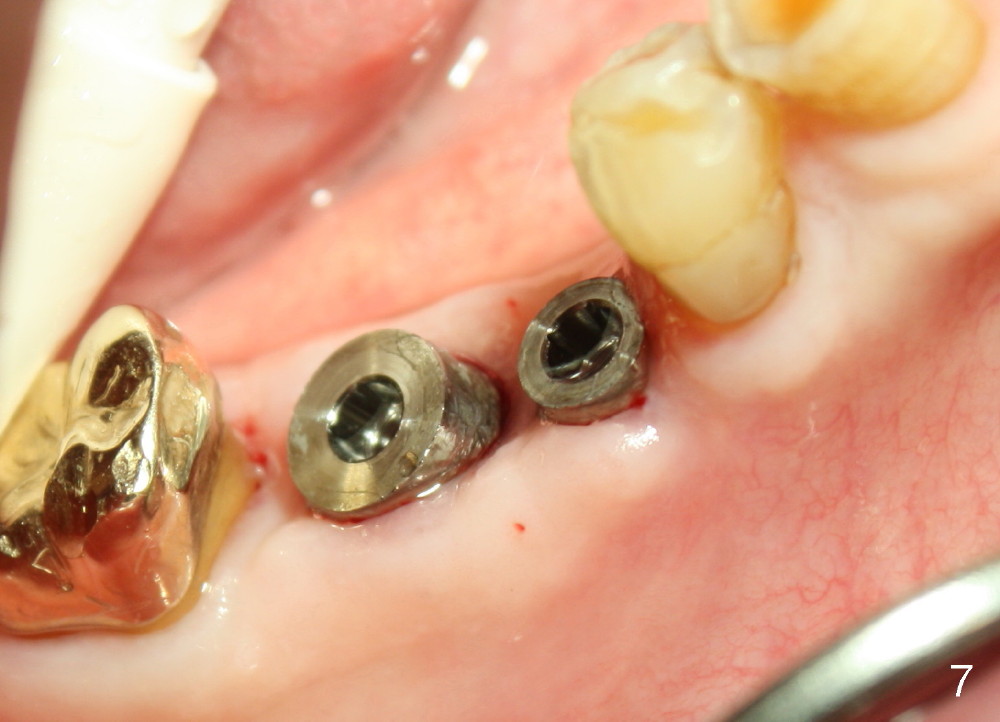

One month after implant placement at the sites of #29,30, the former is found loose (Fig.1,2). It is placed higher than #30. Three weeks later, PA is retaken to confirm that there is space apical to the implant at #29 (Fig.3 double arrows) and that there is distance from the mental loop (yellow dashed line). After infiltration anesthesia, the implant is torqued down initially (compare Fig.4,5) and more (Fig.6,7). To prevent re-loosening, the two implants are splinted (Fig.8).